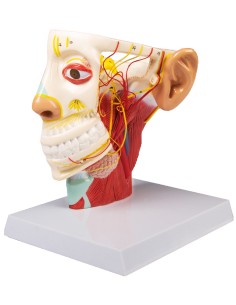

Scopri il Mondo dell’Anatomia con Modelli anatomici di Precisione

Modelli Anatomici Dettagliati per Ogni Necessità

Dal cranio in 22 parti con incastri magnetici ai modelli di colonna vertebrale, da quelli di articolazioni a quelli di cuore, ogni pezzo della nostra collezione è progettato per un’immersione totale nello studio dell’anatomia umana. I nostri modelli, realizzati tramite scansioni di ossa vere, garantiscono un’esperienza tattile autentica e una fedeltà di peso quasi identica agli originali.

Strumenti Didattici Innovativi per l’Educazione e la Pratica Medica

Essenziali per studenti e professionisti, i nostri modelli anatomici sono strumenti didattici che permettono di osservare le strutture anatomiche con precisione, eliminando la necessità di dissezioni o studi invasivi. Sono inoltre utili per spiegare ai pazienti le patologie, rendendo la comunicazione più efficace e risparmiando tempo prezioso.